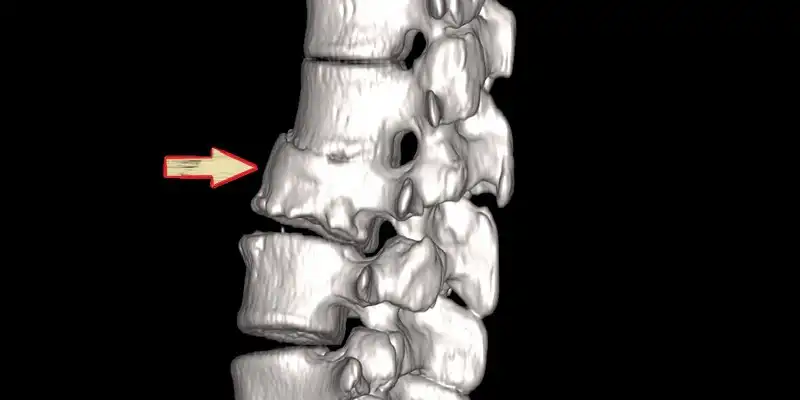

| نواحی شایع درگیری | ستون فقرات (گردن و کمر)، زانو، لگن، انگشتان دست و پا، پاشنه پا |

مفاصل زانو، لگن، ستون فقرات، و انگشتان دست و پا از جمله محلهای شایع برای تشکیل استئوفیت هستند.

در ستون فقرات، استئوفیتها میتوانند باعث تنگی کانال نخاعی و فشار بر اعصاب شوند.

تشخیص:

استئوفیتها با استفاده از روشهای تصویربرداری مانند اشعه ایکس، MRI و CT اسکن قابل تشخیص هستند.